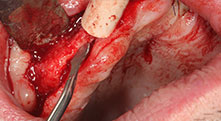

For what indications do you use the saws?

Bratu: We routinely use the instruments for harvesting bone blocks and splitting alveolar ridges. We also use the Piezomed B6/B7 for osteotomy of impacted teeth and removing failed implants. All indications that require deep, clean cuts.